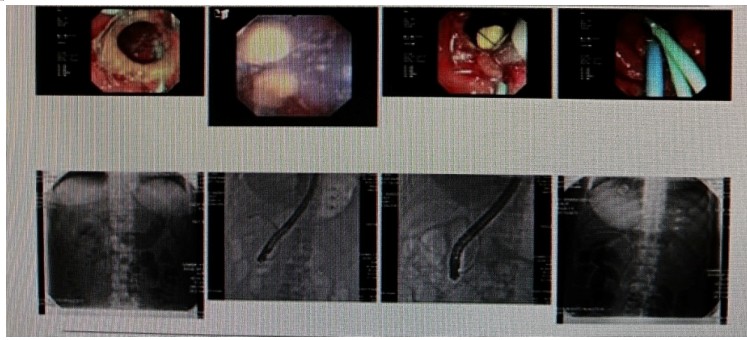

消化內(nèi)科肝病亞??茍F隊詳細討論,分析患者情況后,取消了周女士的肝穿刺活檢檢查,建議患者先行超聲胃鏡下膽胰掃查。在內(nèi)鏡醫(yī)師第三只眼——超聲胃鏡的掃查下,發(fā)現(xiàn)引起周女士肝功能受損的罪魁禍首原來是膽總管末端結石!伍友興主任醫(yī)師帶領團隊給予患者行ERCP下取石后,周女士未再出現(xiàn)腹痛,肝功能恢復正常。

無獨有偶,劉先生也為反復出現(xiàn)肝功能受損到多家醫(yī)院就診檢查,未能找到原因,來到衡陽市中心醫(yī)院消化內(nèi)科就診,希望能在肝穿刺活檢下得出病因。在行肝穿刺活檢之前,醫(yī)生建議劉先生行超聲胃鏡膽胰掃查,發(fā)現(xiàn)引起劉先生反復肝功能受損原因,亦是膽總管結石引起,在ERCP術取石術后,患者肝功能恢復正常,未再出現(xiàn)異常情況。

張丹霞主任醫(yī)師介紹,超聲內(nèi)鏡通過胃十二指腸自然腔道,可以將探頭貼近相應的位置,近距離的觀察胰腺及膽道系統(tǒng),準確捕捉到直徑小于5毫米的胰腺異常病灶及膽道系統(tǒng)病灶。而體表B超常受皮膚、脂肪或腸道氣體干擾。CT或磁共振檢查只能提供靜態(tài)圖像,且對膽胰管陰性結石或是未引起明顯膽管梗阻性的結石檢查有局限性,因此對于有輕微腹痛合并肝功能受損的患者,建議常規(guī)行超聲胃鏡下膽胰掃查。超聲胃鏡、腹部彩超、腹部CT、腹部MRI同為診斷膽管細微病變的四架馬車,在膽總管結石診斷方面,超聲胃鏡膽胰掃查同ERCP一樣,是敏感性高、特異性強的診斷方法。超聲胃鏡發(fā)現(xiàn)可疑病變,可以完成穿刺活檢,還可行囊腫穿刺引流、膽管減壓、消融術等。